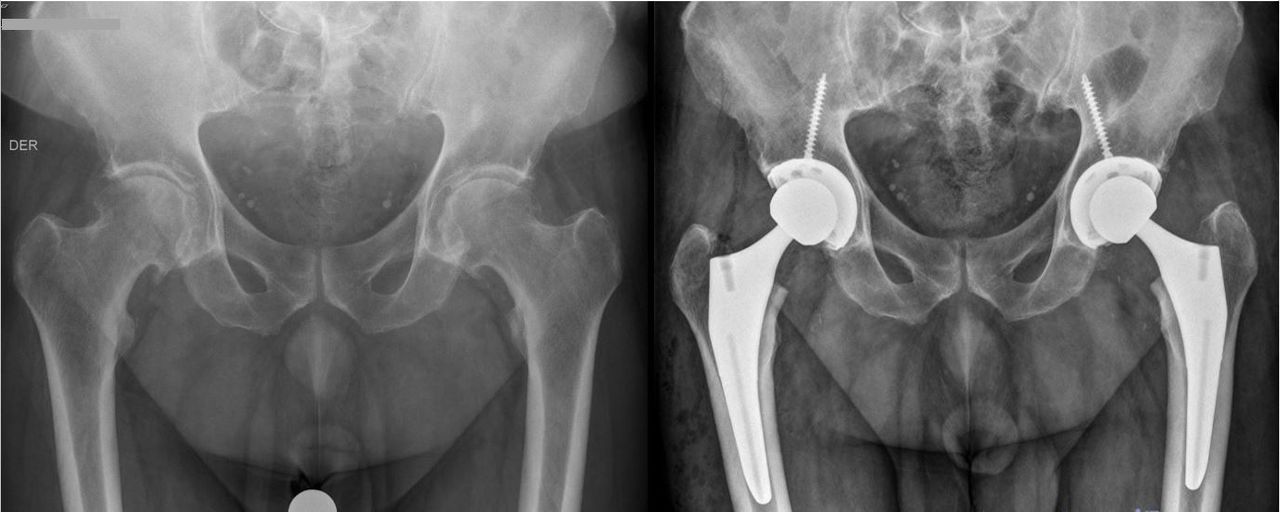

Soy médico traumatólogo especialista en Cirugía de Cadera y Pelvis. Inicié mi formación como médico en la Universidad de Chile, y posteriormente la especialidad de Traumatología y sub-especialidad de Cirugía Reconstructiva de Cadera y Pelvis en la Clínica Alemana – Universidad del Desarrollo.

Mi práctica clínica está enfocada en el manejo integral de patologías de cadera, combinando experiencia quirúrgica, trabajo interdisciplinario y un enfoque personalizado para cada paciente. He realizado estadías de perfeccionamiento en centros de referencia internacional en Estados Unidos y España, especializándome en cirugía protésica, artroscopía de cadera y tratamiento de fracturas complejas.

• Prótesis total de cadera (primaria y de revisión)

• Displasia de cadera y cirugía reconstructiva